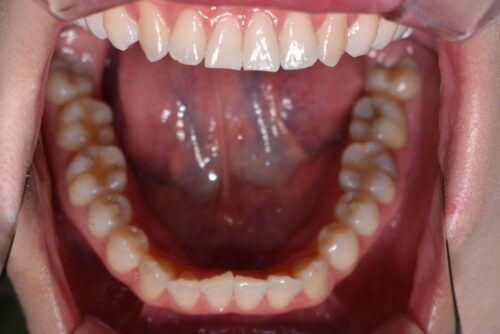

初診時年齢28歳女性

歯のがたつき(叢生)と

出っ歯

と

開咬

を気になさり

巣鴨 ・ 池袋よりひとつ隣駅の東京都豊島区大塚駅すぐの大塚たまみ矯正歯科へ

来院されました。

本症例も

矯正治療の精密検査後

非抜歯矯正治療計画を立案しました。

ワイヤー矯正治療9か月後です。